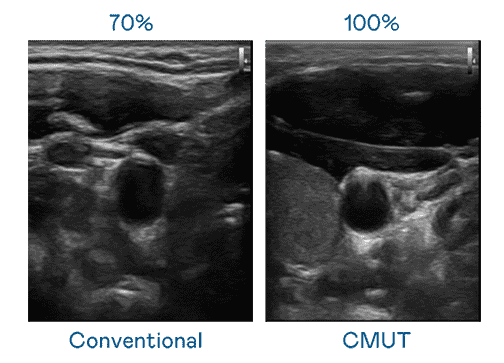

CMUT 技术是一种用电容式微机电元件来产生超音波讯号的技术。。。与传统 PZT 压电式技术相比,,,,CMUT 频宽增加 30%,,,更宽频的超音波讯号让影像解析度大幅提升,,,是实现高影像品质医疗超音波扫描、、促进精准医疗发展的关键技术。。。。

大频宽带来超清晰影像

超音波影像的解析度高低,,,,首先取决于探头能发出的讯号频宽。。z6尊龙 CMUT 可提供高清晰的超音波讯号,,提供高频宽、、、、高灵敏度、、、影像纹理细节更高的超音波影像,,协助医护人员缩短影像判读时间及利用精准的医疗影像进行诊断。。。